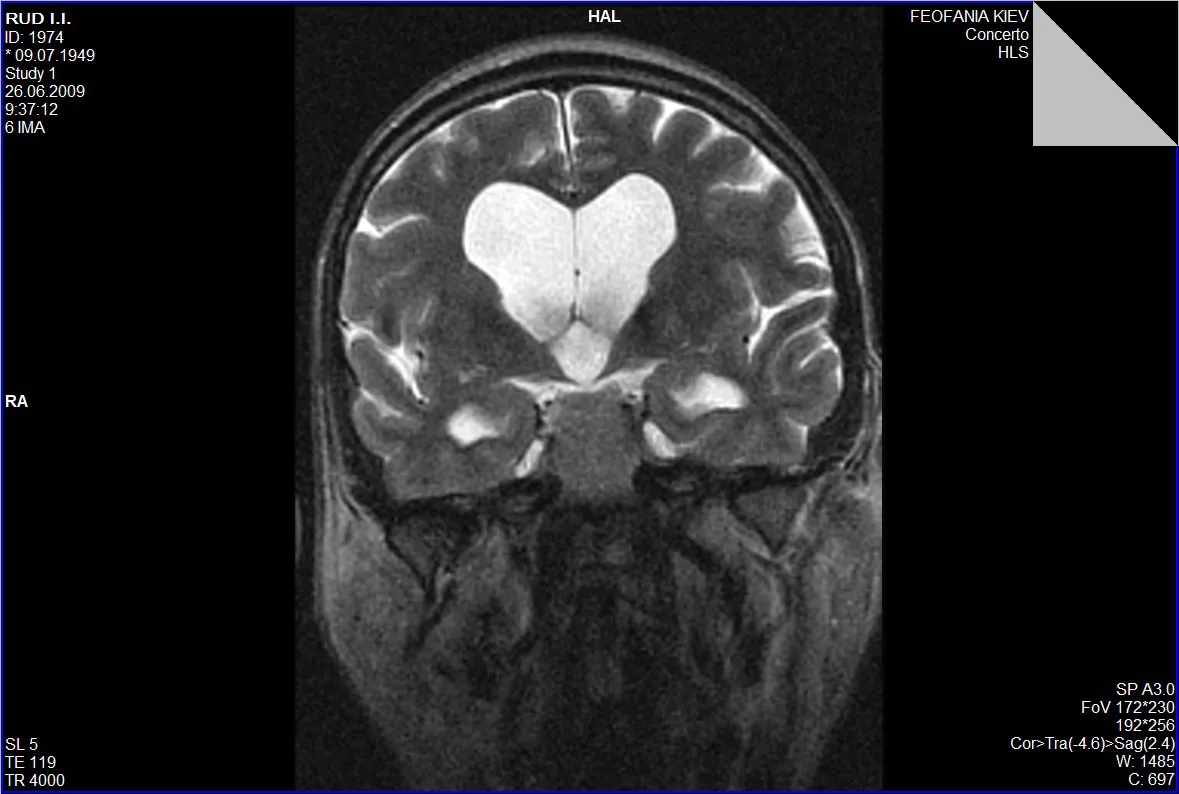

Гідроцефалія, або водянка головного мозку, — це патологічний стан, який характеризується накопиченням цереброспінальної рідини (ліквору) у шлуночках мозку та міжоболонкових просторах.

За патогенезом гідроцефалію розрізняють двох видів: окклюзійна гідроцефалія (коли є перешкода всмоктування ліквору у кровоносну систему мозку від місця її секреції у шлуночках до місця її всмоктування – у субарахноїдальних системах/субарахноїдальному просторі) та арезорбтивна гідроцефалія (у разі, коли порушений сам процес абсорбції ліквору).

Причини гідроцефалії різноманітні: вроджені вади розвитку головного мозку (мальформації Кіарі 1-го та 2-го типів, миєломенингоцеле, первинний стеноз водопроводу головного мозку, мальформація Денді- Уокера (атрезія отворів Люшка та Мажанді); набуті гідроцефалії інфекційного генезу (після перенесених менінгіту, паразитарних захворювань (наприклад, цистицеркоз); гідроцефалія внаслідок крововиливів у головний мозок (інсульти, розриви аневризм, внутрішньошлуночкові крововиливи тощо); при непухлинних та пухлинних захворюваннях головного мозку, нейросаркоідозі; гідроцефалії, пов’язані із спинальними пухлинами.